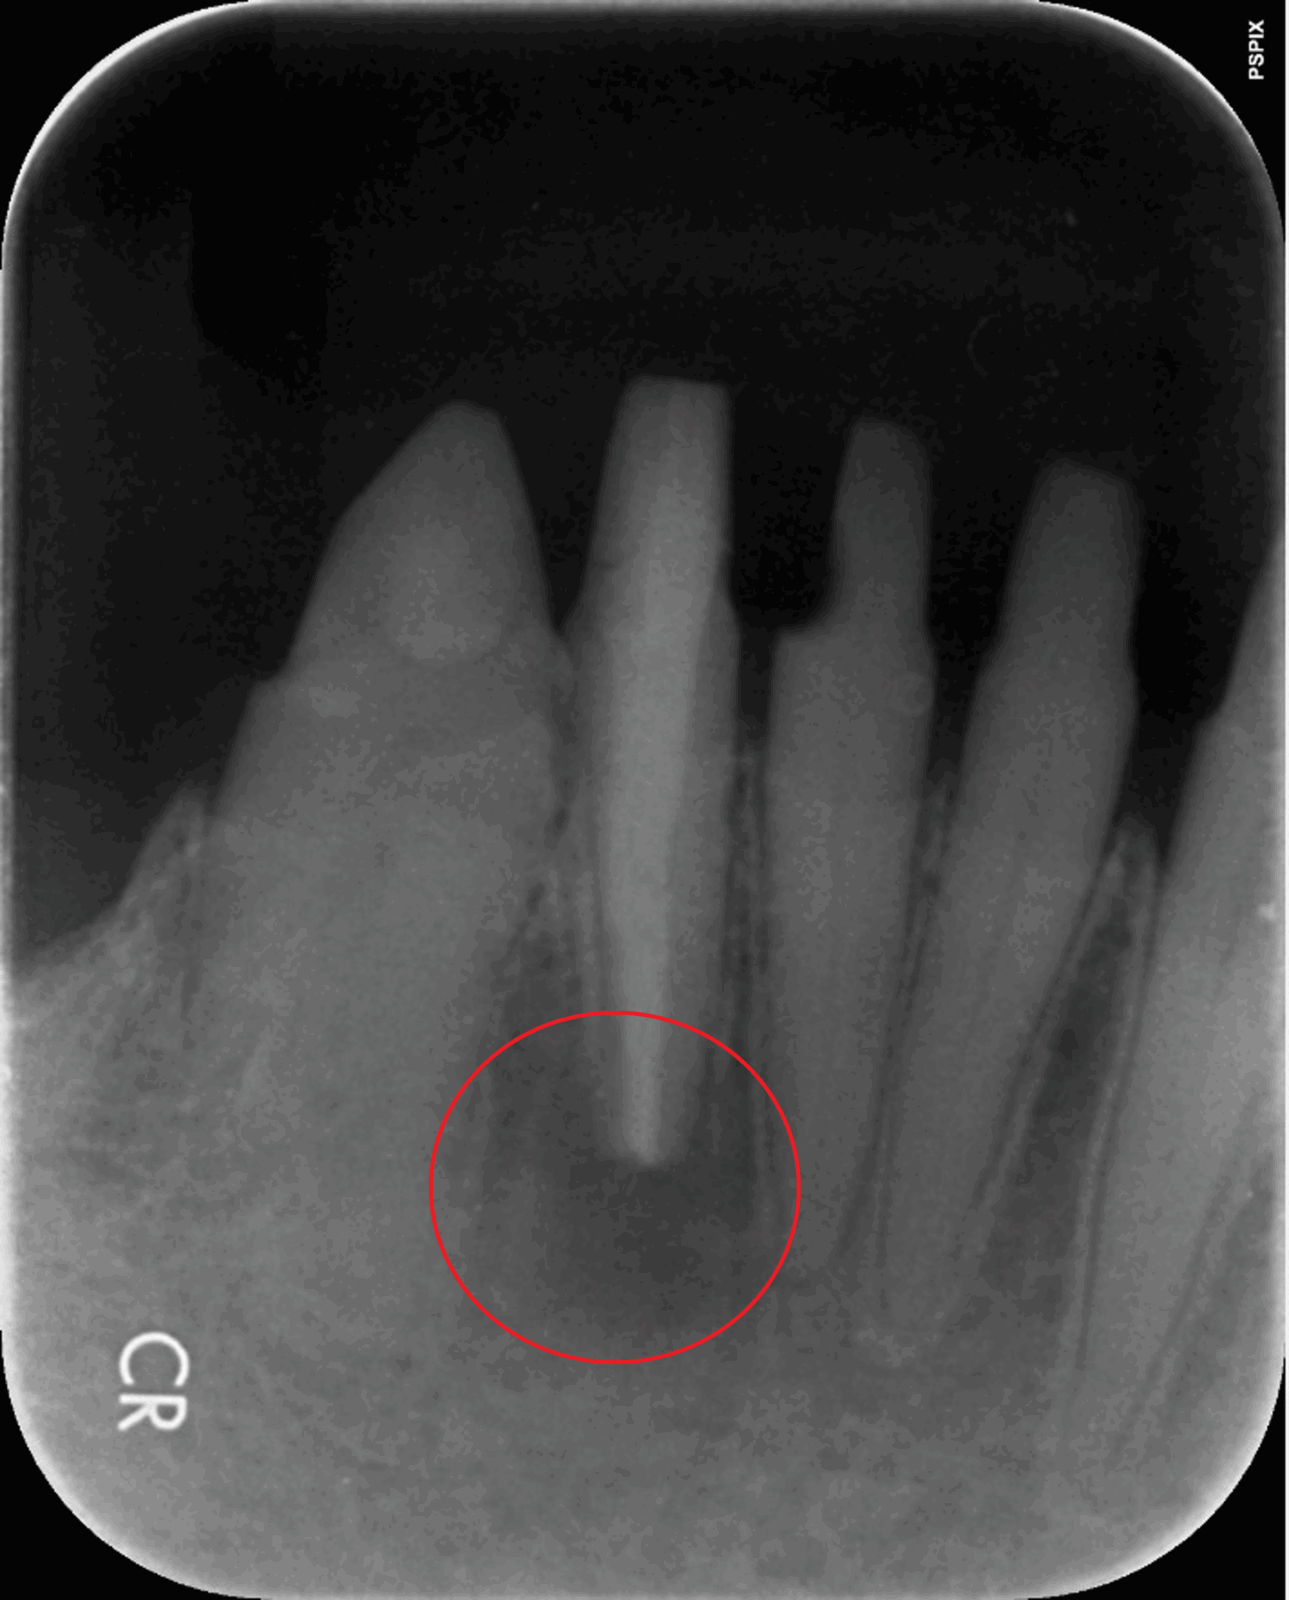

次の画像は、同じ患部をCTとレントゲンで撮影した画像です。

• 比較

「左」の写真がCTで、「右」の画像がレントゲンで撮影したものです。

赤丸で囲んだところには、黒い影が見えます。ここには炎症が起こっているのですが、右の写真には影がありません。つまり、2次元のレントゲンだけで診断した場合、問題のある部分は治療しない選択をするため、最終的には抜歯の運命をたどるケースです。